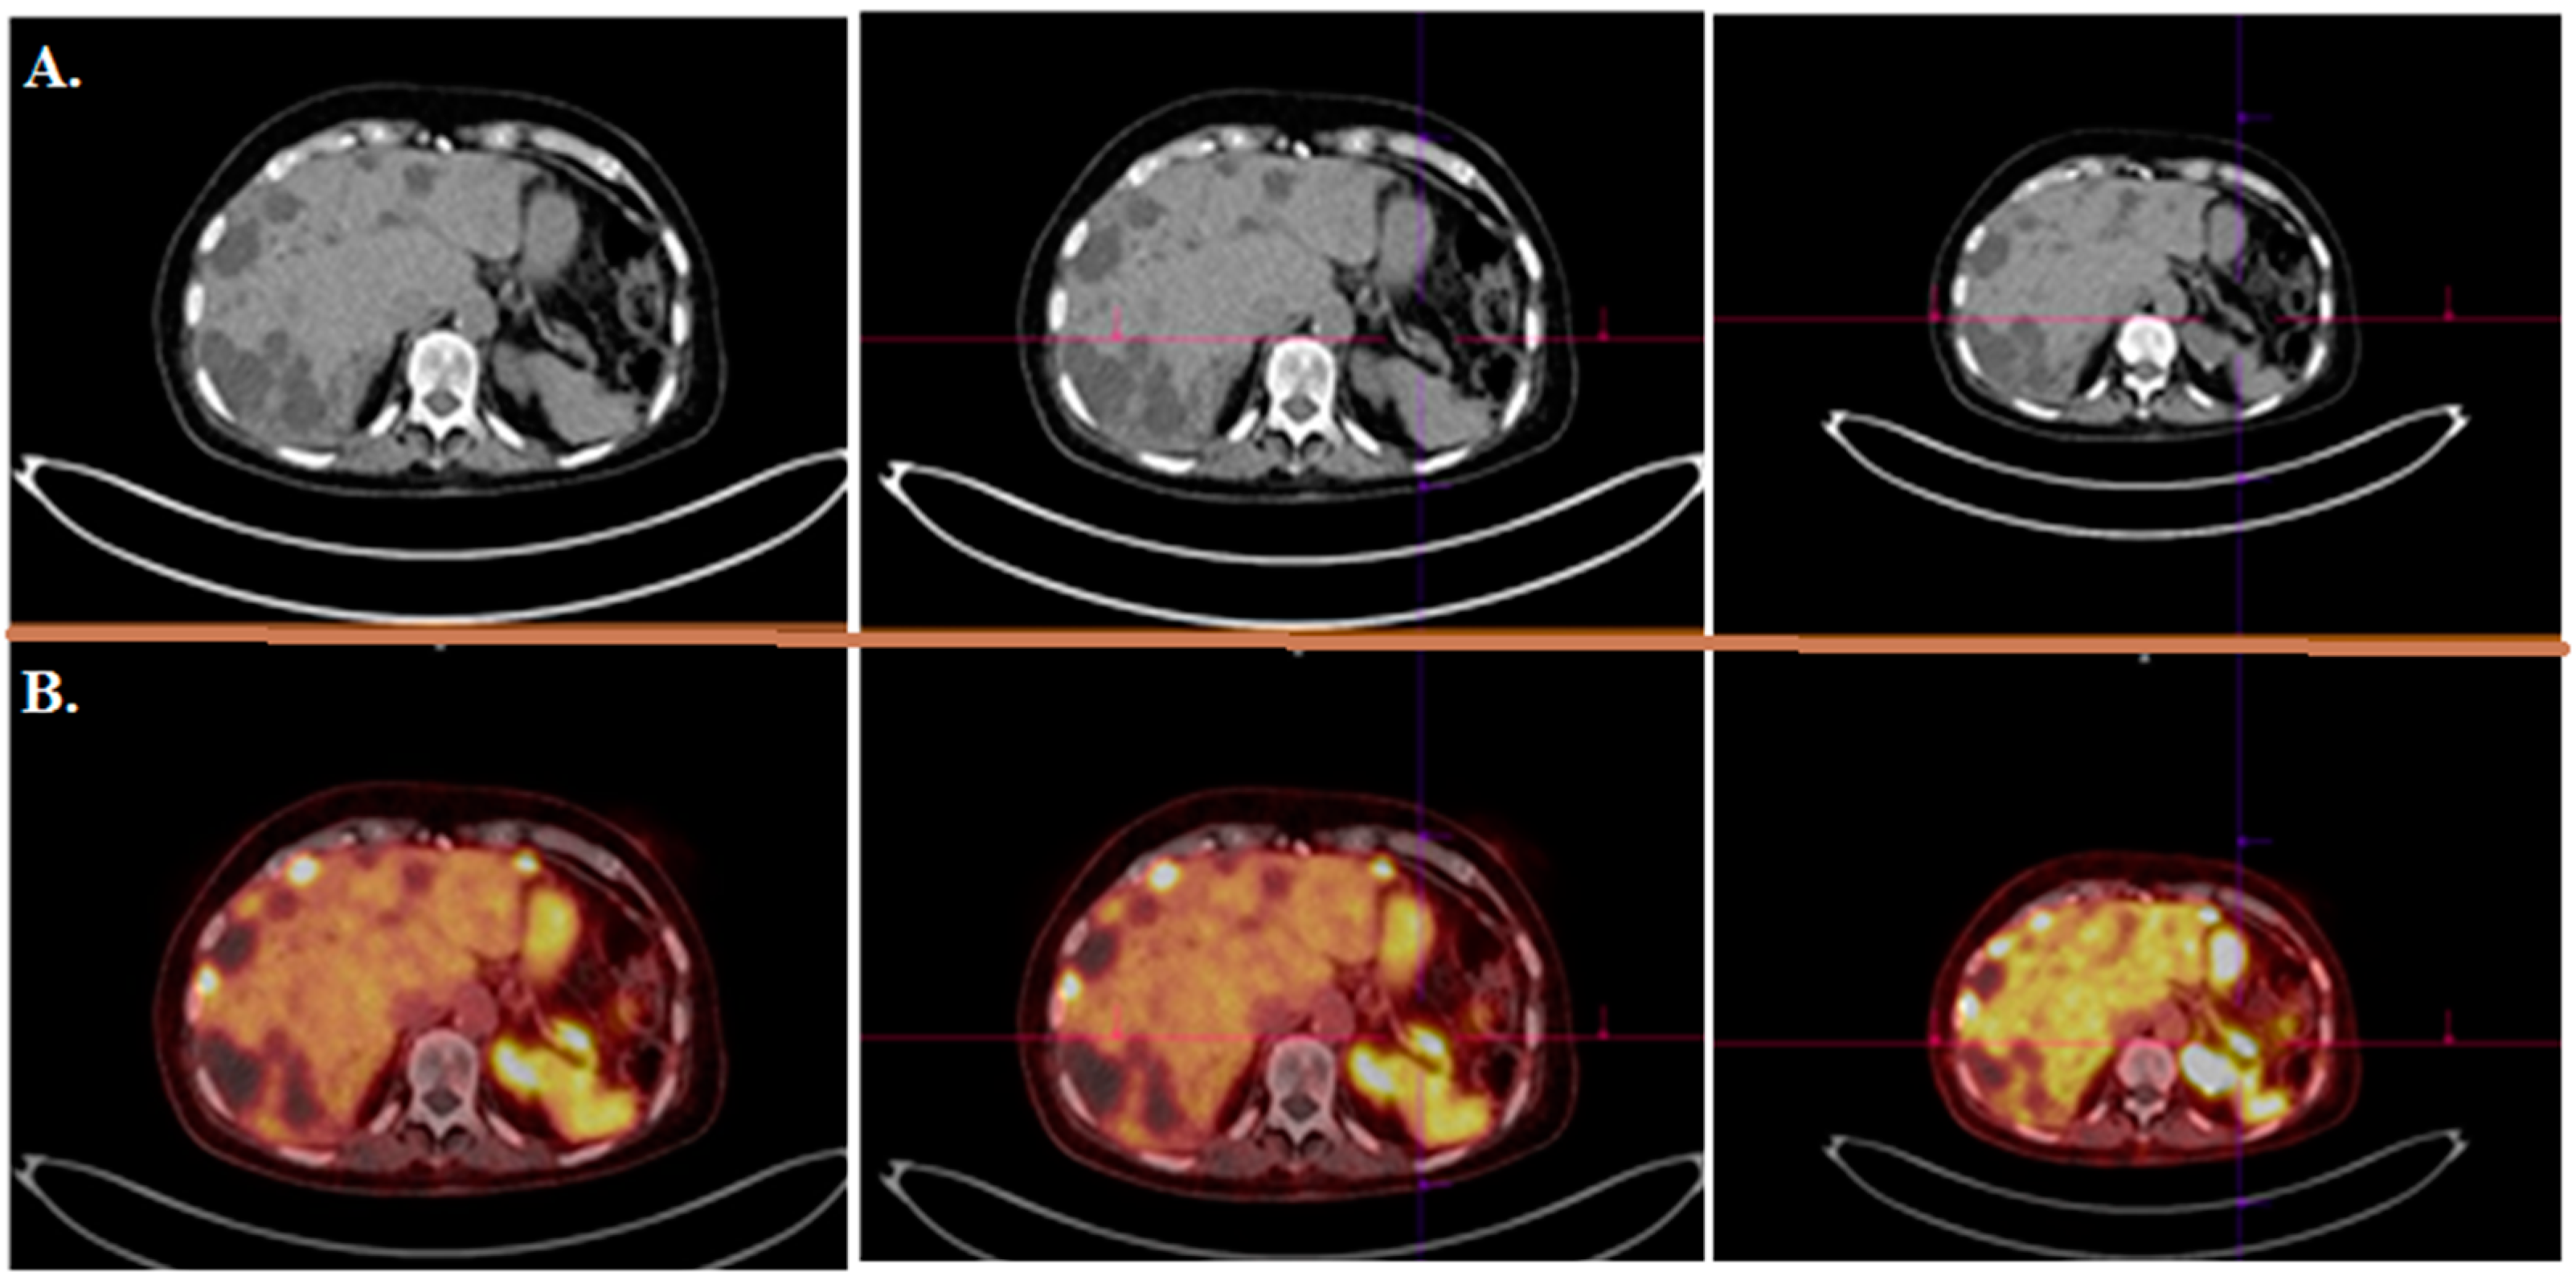

- Mirzaei, S.; Revheim, M.-E.; Raynor, W.; Zehetner, W.; Knoll, P.; Zandieh, S.; Alavi, A. 64Cu-DOTATOC PET-CT in patients with neuroendocrine tumors. Oncol. Ther. 2020, 8, 125–131. [Google Scholar] [CrossRef] [Green Version]

| [64Cu]Cu-DOTA-TOC | NET | 33 | 2019 | High detection rate and high target to background ratio in images raised [64Cu]Cu- DOTA-TATE as a promising and safe radiolabeled SST derivative for NET detection | [22] |